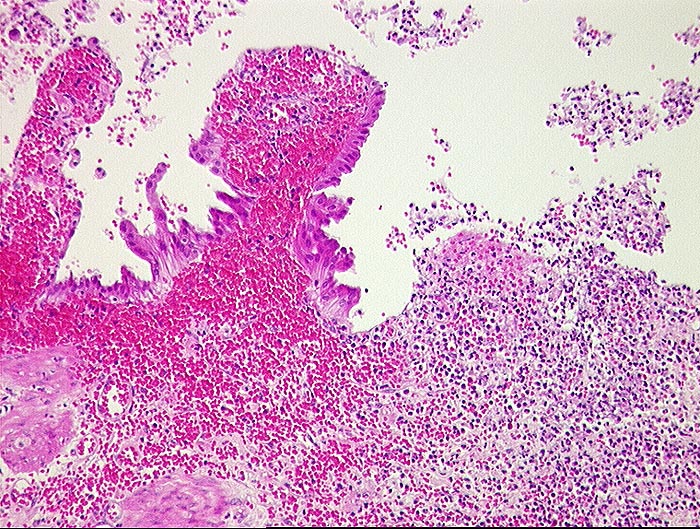

Hämorrhagische akute Cholezystitis

Ulzerierte Gallenblasenschleimhaut mit frischen Einblutungen in der Lamina propria.

Akute Cholezystitis.